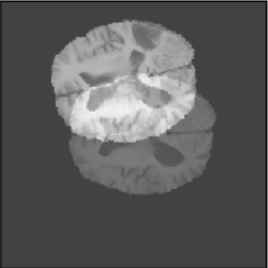

To illustrate the performance of the proposed technique for clinical applications, MR images were chosen. The performance of the technique was tested by registering multi-modal MR image pairs. In a clinical setup, it is common practice to register images or volumes acquired from different imaging modalities or MR sequences. Figure 3 illustrates the degree of overlap between moving images (a) T2 and (f) T1 weighted sequence on fixed images (b) T2 and (g) T2 weighted sequence respectively. It was observed using the registration proposed in this manuscript, the dice score improved from 0.44 (prior to registration) to 0.91 (post registration) for multimodal sequences. On the BraTs data, figure 4 (a-d) illustrates the performance of our method based on other metrics such as Dice, SSMI, MI, and MSE respectively. As the key points were generated by utilizing only the feature maps of the initial two layer of the network, the spatial dimension of the data has little impact on the performance. Unlike other CNN based technique which considers the entire image for estimating the transformation parameters, our method requires CoMs which reduces the dimensionality from (m n n) to (m 2), where m denotes the number of feature maps and n is the pixel dimension of the feature map. This aids in lowering execution time drastically. The proposed pipeline also consists of an uncertainty estimator. uncertainty maps illustrated in all the above examples show the region of higher variance in registration, which in turn suggests surgeons/ observers to make better decisions. Pixel region with red color indicates the larger variance region while blue indicated low variance region. For example in figure 3 (e) shows that the central region of the brain has higher pixel-wise variance as compared to the outer part of the brain. The performance of the algorithm on volumes on the same modality is illustrated in figure 3 (a-e)